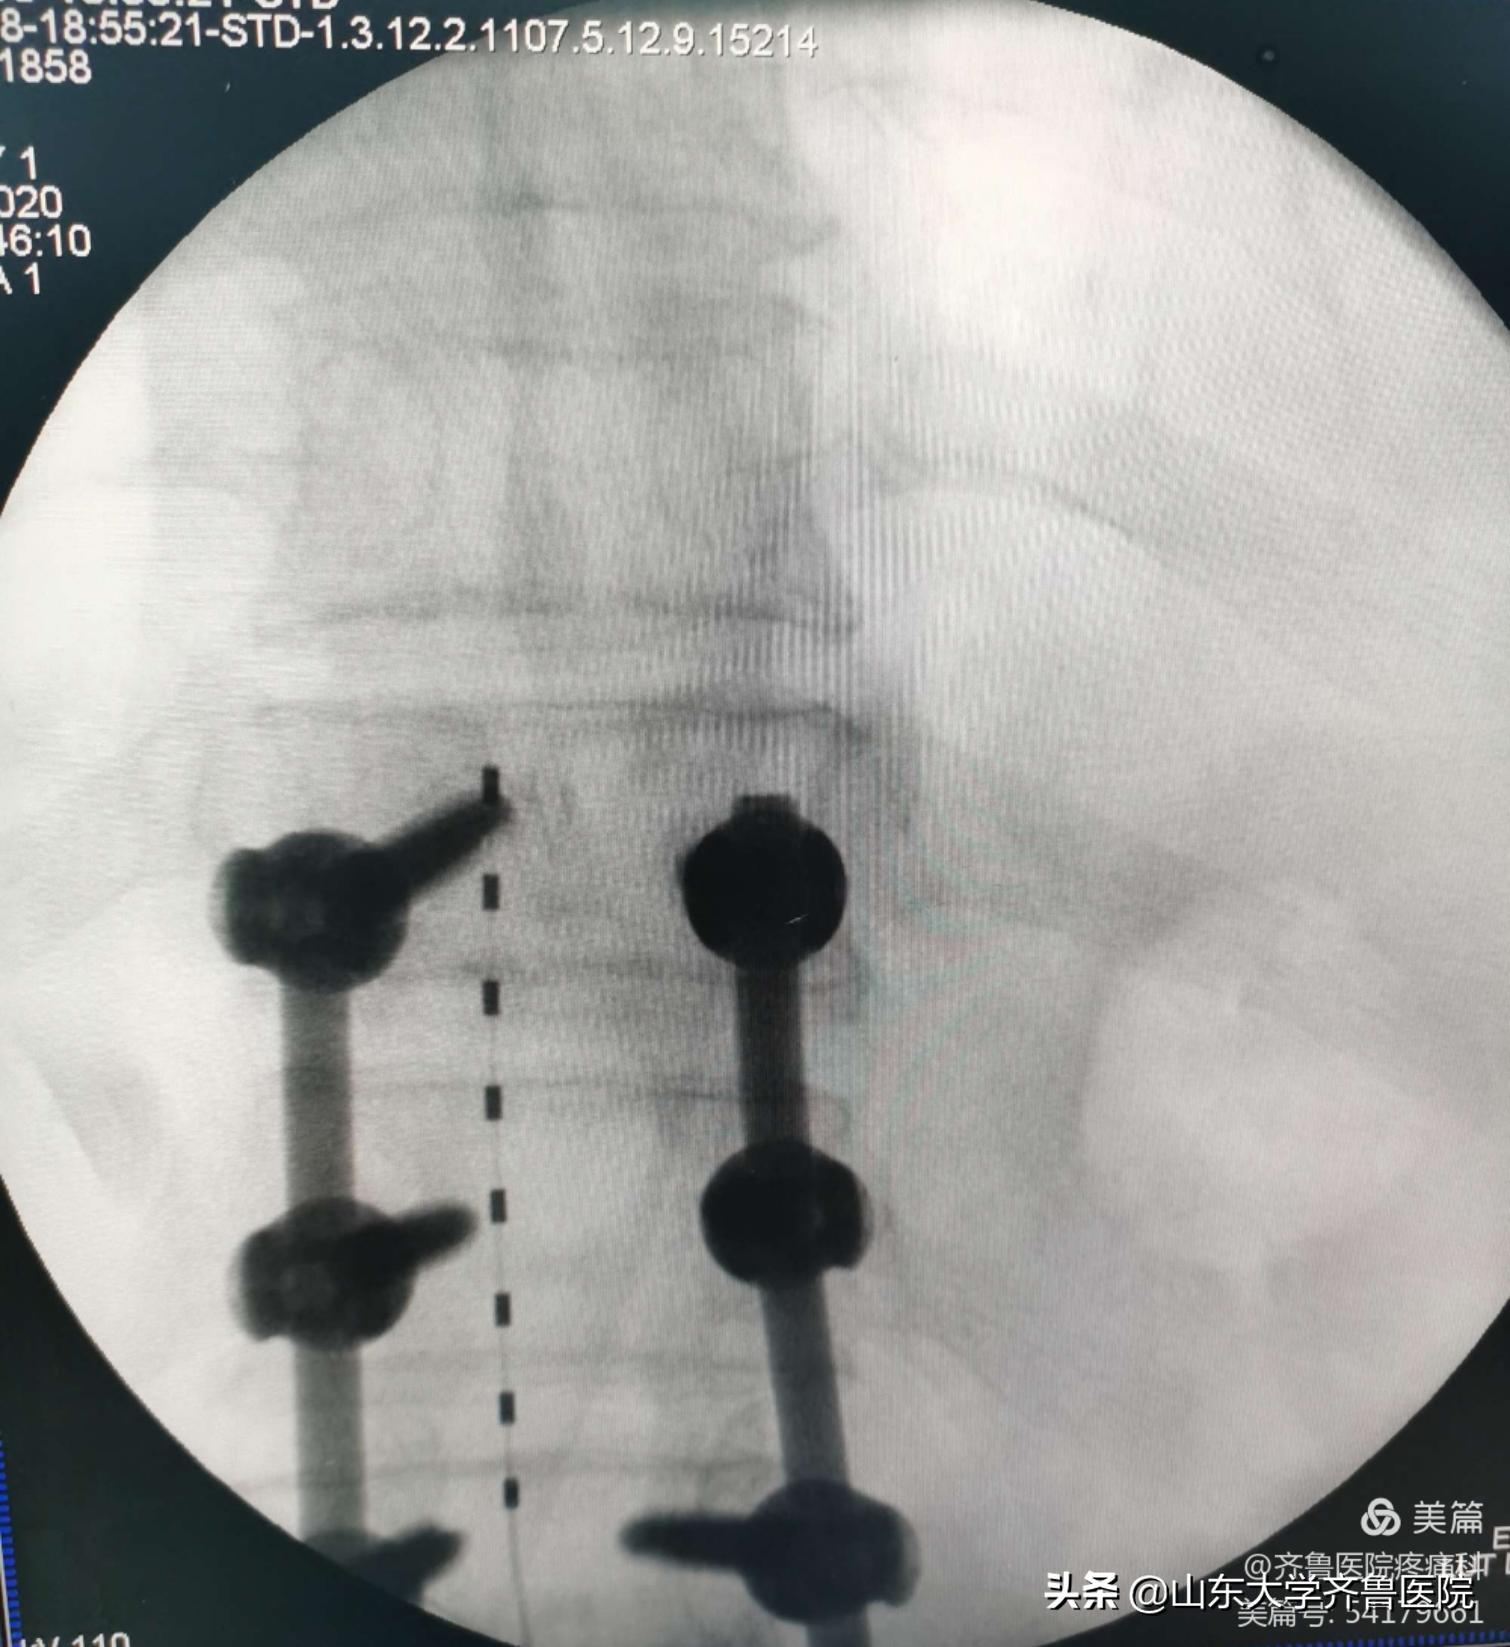

图2.颈髓损伤后顽固性疼痛患者术中穿刺植入针状电极

图3.电极测试良好